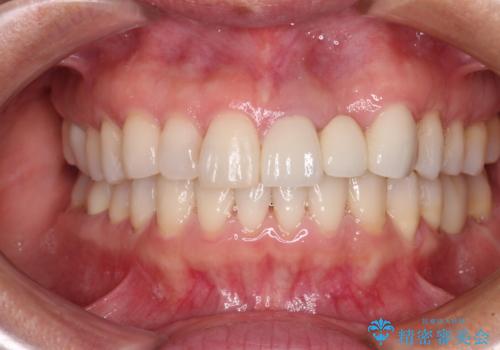

[ 矯正と補綴、総合歯科治療 ] クロスバイトを避ける前歯部審美ブリッジ

![[ 矯正と補綴、総合歯科治療 ] クロスバイトを避ける前歯部審美ブリッジの症例 治療後](https://seimitsushinbi.jp/wp/wp-content/uploads/2021/07/fcd77503a97e2f3a648f6e8698e34626-500x350.jpg?v=1626697051)